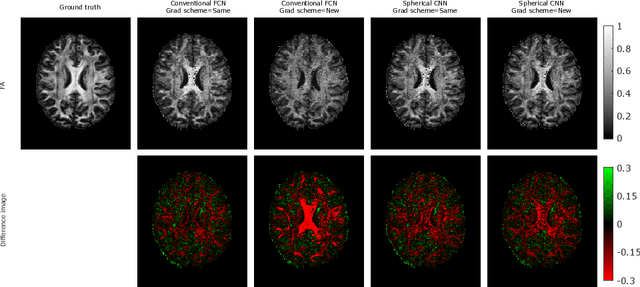

Abstract:This paper demonstrates spherical convolutional neural networks (S-CNN) offer distinct advantages over conventional fully-connected networks (FCN) at estimating scalar parameters of tissue microstructure from diffusion MRI (dMRI). Such microstructure parameters are valuable for identifying pathology and quantifying its extent. However, current clinical practice commonly acquires dMRI data consisting of only 6 diffusion weighted images (DWIs), limiting the accuracy and precision of estimated microstructure indices. Machine learning (ML) has been proposed to address this challenge. However, existing ML-based methods are not robust to differing dMRI gradient sampling schemes, nor are they rotation equivariant. Lack of robustness to sampling schemes requires a new network to be trained for each scheme, complicating the analysis of data from multiple sources. A possible consequence of the lack of rotational equivariance is that the training dataset must contain a diverse range of microstucture orientations. Here, we show spherical CNNs represent a compelling alternative that is robust to new sampling schemes as well as offering rotational equivariance. We show the latter can be leveraged to decrease the number of training datapoints required.